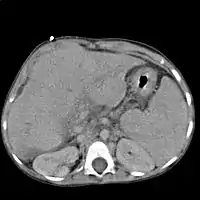

| 肝硬化患者的腹部,有大量腹水及明顯可見的靜脈 | |